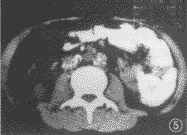

图5 CT平扫。示腹主动脉周围多个淋巴结肿大,并见多发斑点灶钙化灶